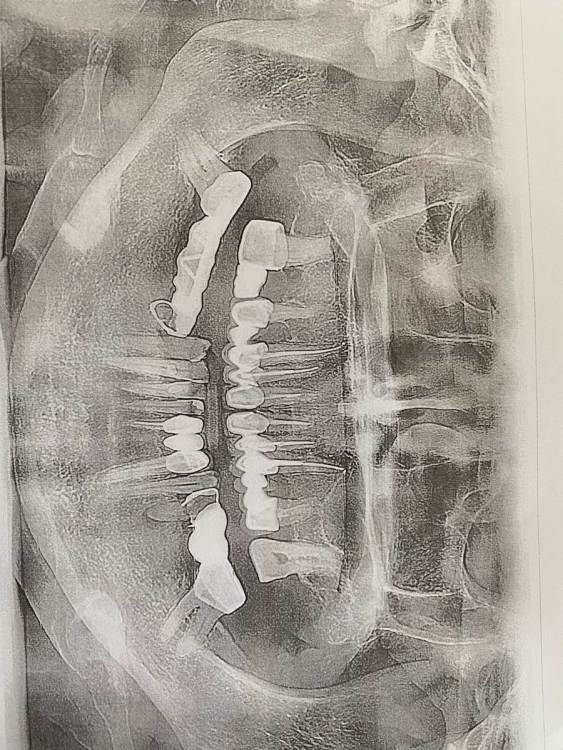

IvanK Опубликовано 5 ноября, 2022 Поделиться Опубликовано 5 ноября, 2022 Здравствуйте , У меня видео не воспроизводятся.. Ра разминку шеи спасибо)) Но ОПТГ смотреть удобнее, когда оно расположено правильно)) Ссылка на комментарий